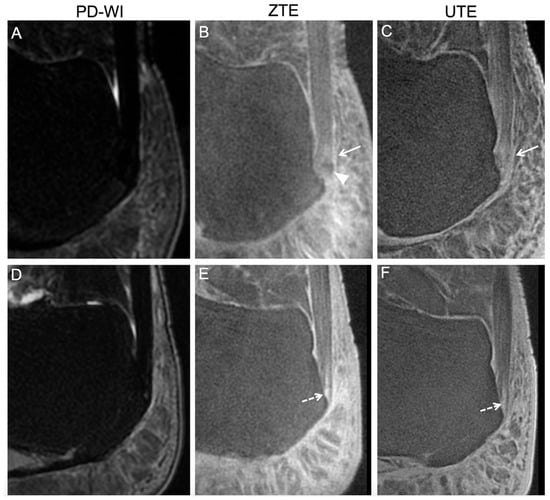

Regarding the PCa, there were no abnormal findings using PD-WI; however, the radiologists described 3/38 (7.9%) as doubtful of pathological findings with the UTE sequence and 5/50 (10%) with ZTE. The rate of false positive findings was not significantly different across the three sequences (p = 0.2818).

Regarding the SCa, there was one abnormal finding using PD-WI; however, the radiologists described 5/38 (13.2%) as doubtful of pathological findings with the UTE sequence and 9/50 (18%) with ZTE. The rate of false positive findings was significantly different across the three sequences (p = 0.0045). In paired post-hoc adjusted analyses, there was no significant difference in the rate of false positive findings with UTE compared to PD-WI, ZTE compared to PD-WI (p = 0.1944 and p = 0.1944, respectively), and between UTE and ZTE (p = 0.9279).

Regarding the ECa, there was 1/50 (2%) abnormal finding using PD-WI; however, the radiologists described 8/38 (23.7%) as doubtful of pathological findings with the UTE sequence and 17/50 (34%) with ZTE. The rate of false positive findings was not significantly different across the three sequences (p = 0.0746).

Regarding follow-up questionnaires, 43/50 (86%) answered them. One volunteer declared the appearance of hindfoot pain about one year after his MRI, which revealed, at that time, abnormal findings on UTE and ZTE sequences (but not on PD-WI) at PCa and SCa locations.

Figure 4 and Figure 5 illustrate the MRI findings described as pathological. Regarding the five patients with abnormal findings on the ECa with both UTE and ZTE, the retrospective reading confirmed the presence of high SIs of the ECA and Achilles tendinous fibers surrounding enthesophytes (Figure 4). Regarding the two volunteers with abnormal findings on the SCa and PCa on both UTE and ZTE sequences (including the volunteer who developed hindfoot pain one year later), the retrospective reading confirmed the presence of focal erosion at the SCa and high SIs of the PCa and its surrounding fibers (Figure 5).

Figure 5. Abnormal findings in asymptomatic volunteers involving the enthesis fibrocartilage reported during the consensus reading. The healthy volunteers were a 42-year-old overweight woman (top row) and a 51-year-old man (bottom row). On proton density weighted imaging (PD-WI), no abnormal findings were described for either patient (A,D). However, the first patient demonstrated a focal ossification (white arrow head) and high signal intensities on ZTE and UTE (white arrows) (B,C) at the location of the enthesis fibrocartilage. The second patient displayed a linear fissure at the enthesis fibrocartilage on ZTE (E) and UTE (F). Later, during the follow-up, he declared hindfoot pain.